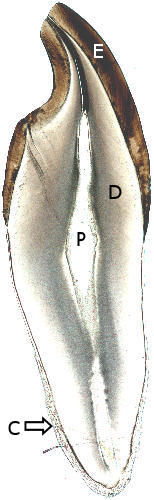

| Longitudinal ground section of a tooth |

| Medium magnification of a longitudinal ground section of a tooth |

Identify the lines of Retzius and dentine canals. |